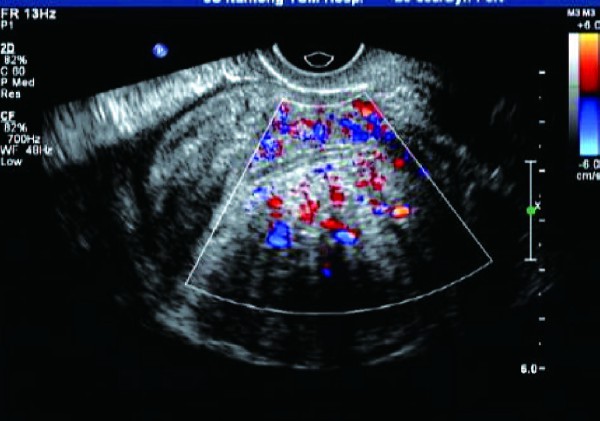

即子宫腺肌瘤,呈边界不清的团块状回声,呈不均质高回声,病灶与正常肌层间没有清晰的边界,即无包膜回声;彩色血流信号丰富,病灶周围无环状彩色血流信号。

子宫肌瘤:①子宫肌瘤可见假性包膜,边界清晰;子宫腺肌症无包膜,与周围组织界限不清。②子宫肌瘤以低回声较为多见,多成旋涡样改变;子宫腺肌症多以弱强回声多见,无明显旋涡状结构。③子宫肌瘤周边血供多于内部,周围有环状血流信号;子宫腺肌症周围无环状彩色血流信号。

经阴道彩色多普勒超声能清晰显示子宫肌层病变的大小、部位、范围,而且能清晰显示其内部结构变化。超声检查时重点视察子宫肌层病灶回声、病灶周边无包膜及病灶内小片状血流信号等特征性表现,能提高诊断符合率。